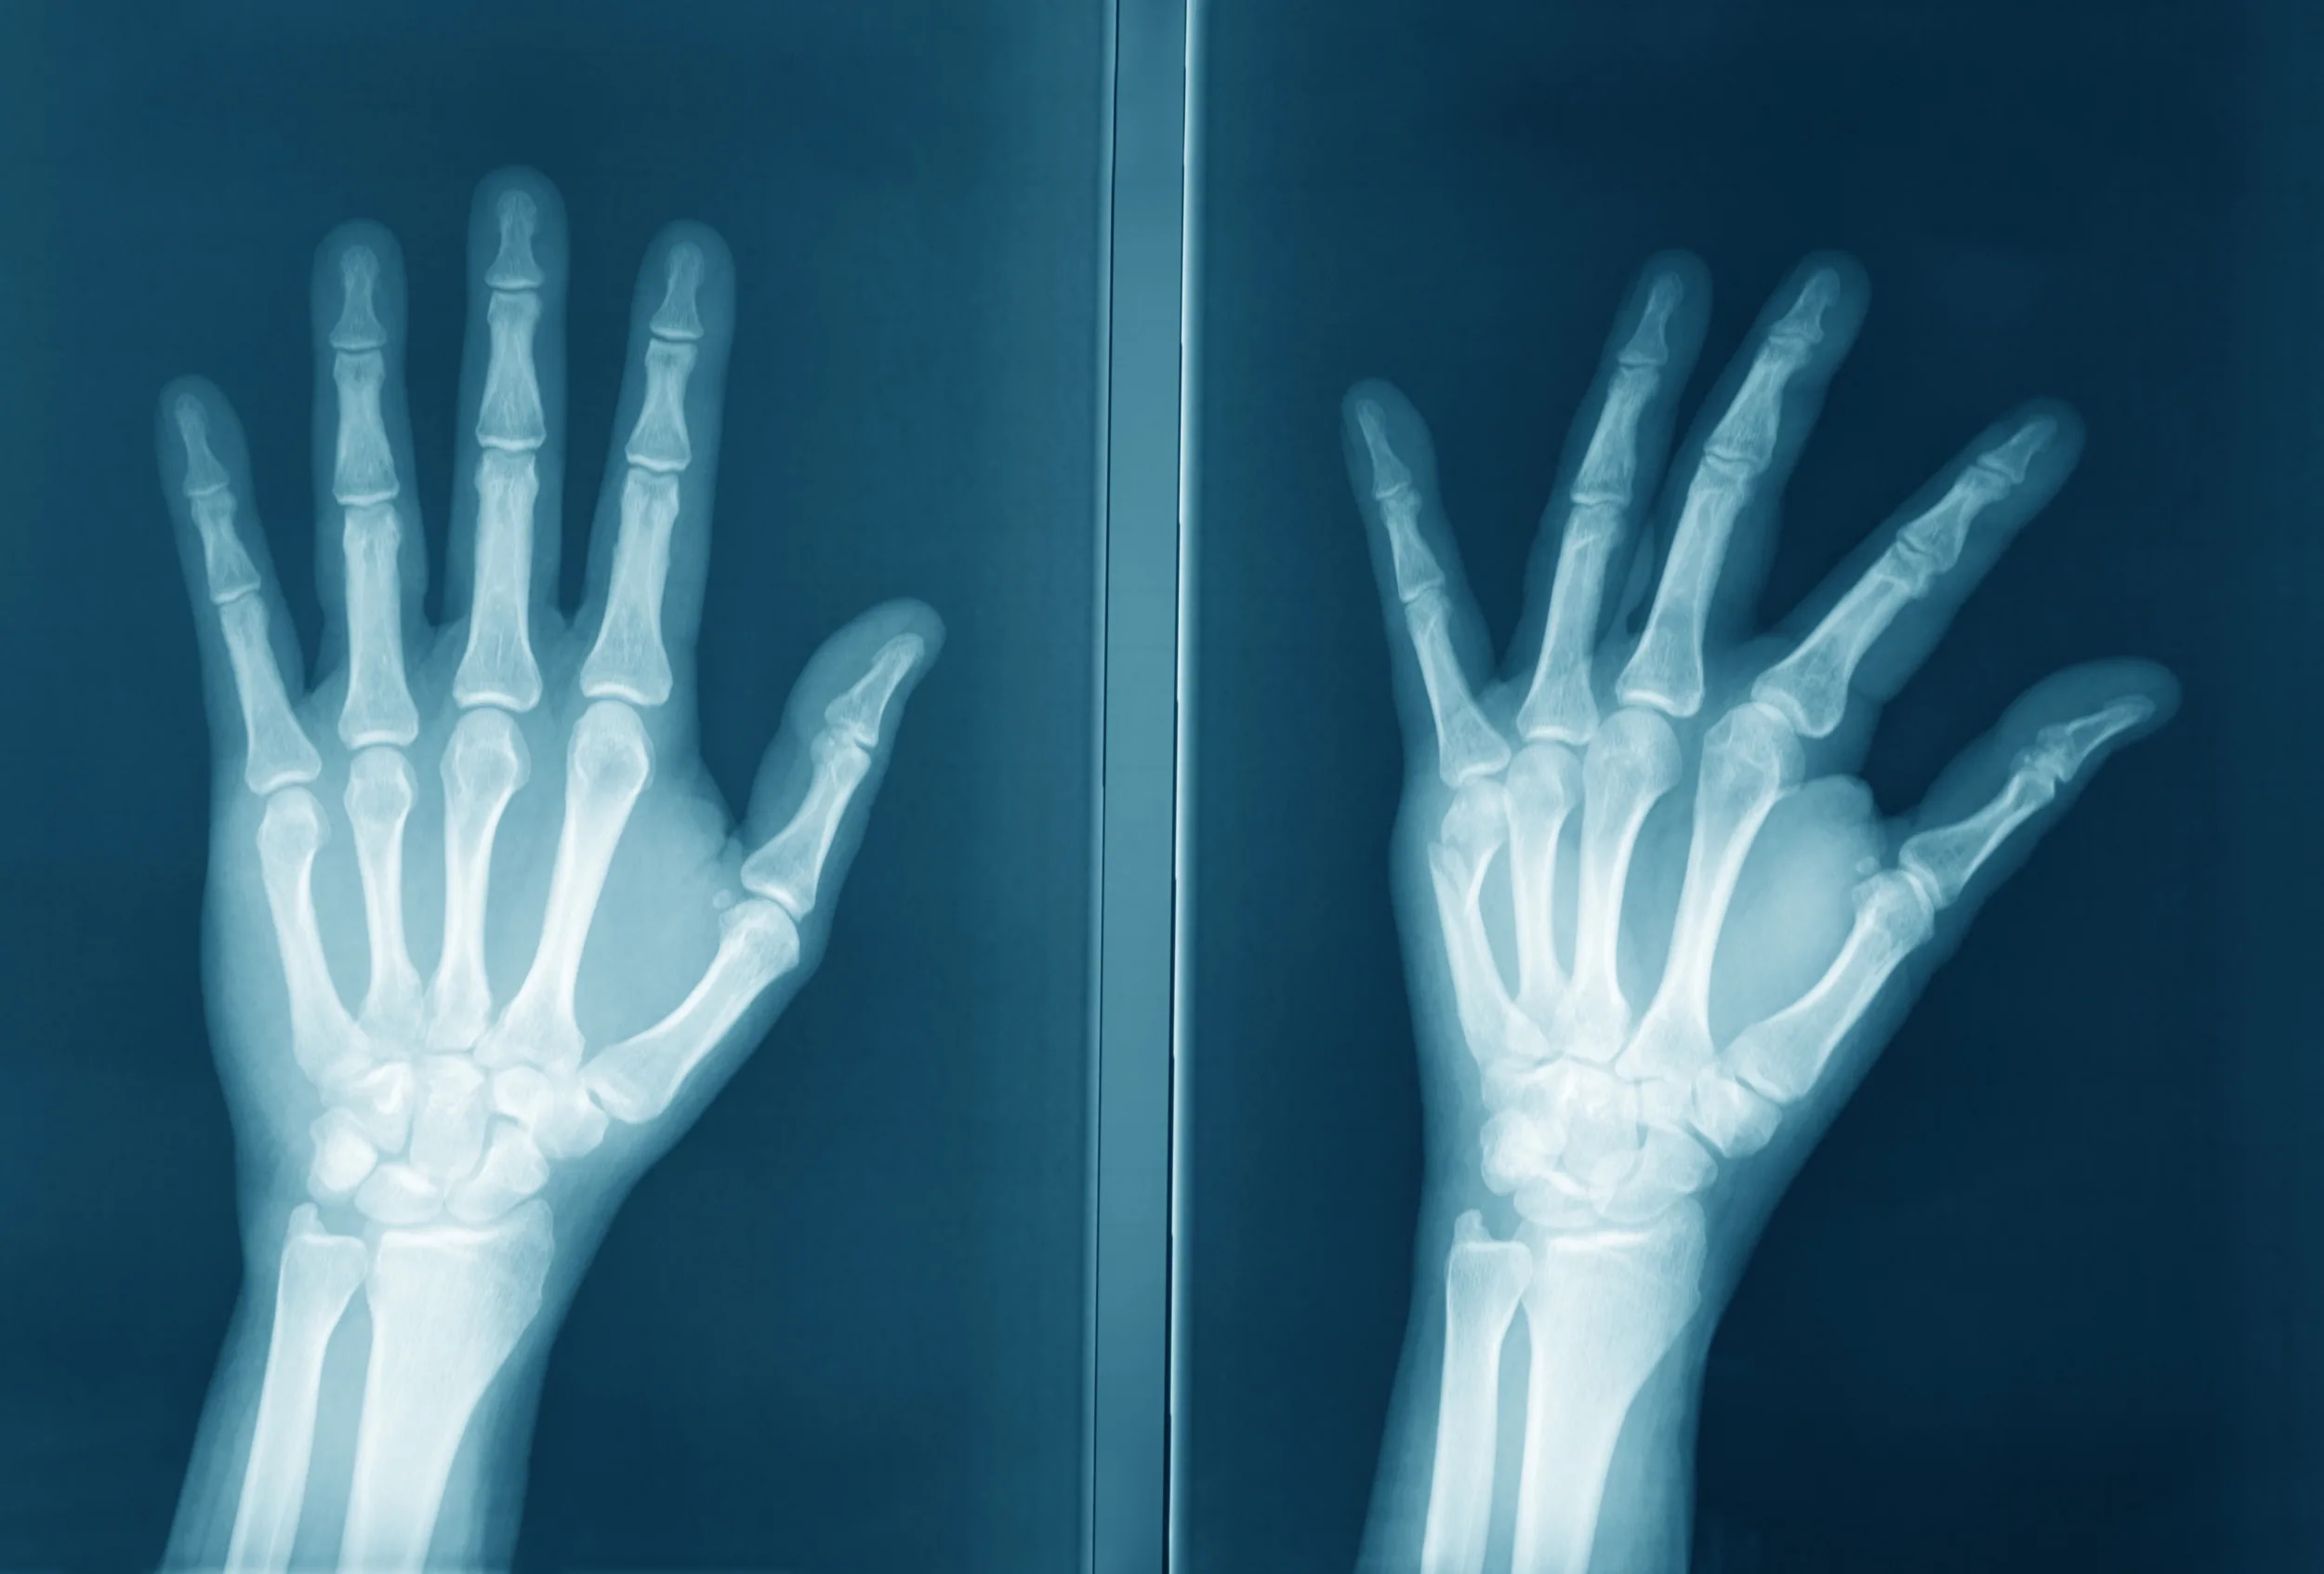

Рентген фаланг пальцев

Рентген пальцев позволяет выявить травмы стопы или кисти, патологию соединительной ткани (например, системная склеродермия), доброкачественные и злокачественные опухоли костной и хрящевой ткани, врожденные аномалии развития и заболевания (ревматоидный артрит, псориатический артрит, остеоартроз, подагра, остеомиелит фаланг пальцев и др.). В Клинике Ильи Труханова в Куркино можно сделать рентгенографию пальцев верхних и нижних конечностей.

Перед исследованием нужно снять кольца, украшения и металлические предметы с пальцев, при диагностике стопы — носки и обувь. На рабочий стол рентген-аппарата или специальную подставку кладется ладонь или ставится стопа. Снимки выполняются в 2 проекциях, чтобы получить максимум информации. Исследование занимает 10-15 минут.